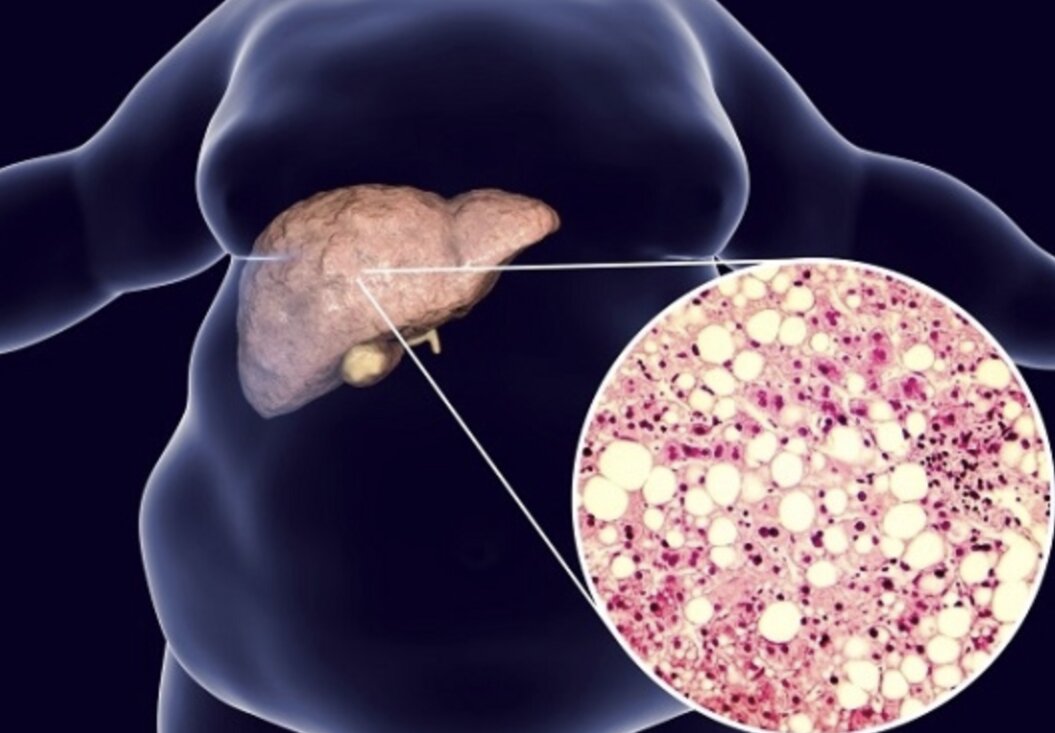

Gan nhiễm mỡ vốn là một vấn đề phổ biến ở người béo phì, bởi khi lượng mỡ trong cơ thể tăng cao, nó tích tụ ở gan, gây áp lực, làm giảm chức năng và sức sống của gan. Tuy nhiên, thực tế hiện nay, gan nhiễm mỡ đang xuất hiện ngày càng nhiều ở những người không béo phì. Nguyên nhân chính là do thói quen ăn uống không lành mạnh, đặc biệt là tiêu thụ quá nhiều dầu mỡ, rượu bia, thịt mỡ… Những thói quen này gây tích tụ mỡ trong gan, làm gan suy yếu dần mà không nhất thiết thể hiện qua cân nặng cơ thể.

PGS. TS. Nguyễn Thị Thanh Hương (chuyên gia Gan mật, Bệnh viện Bạch Mai) cho biết: Gan nhiễm mỡ hiện không còn là bệnh chỉ của người béo phì hay thừa cân. Những người gầy cũng có thể mắc, đặc biệt nếu chế độ ăn nhiều đồ chiên rán, rượu bia, ít vận động. Vì vậy, kiểm soát chế độ ăn uống là bước đầu tiên và quan trọng nhất để cải thiện sức khỏe gan.